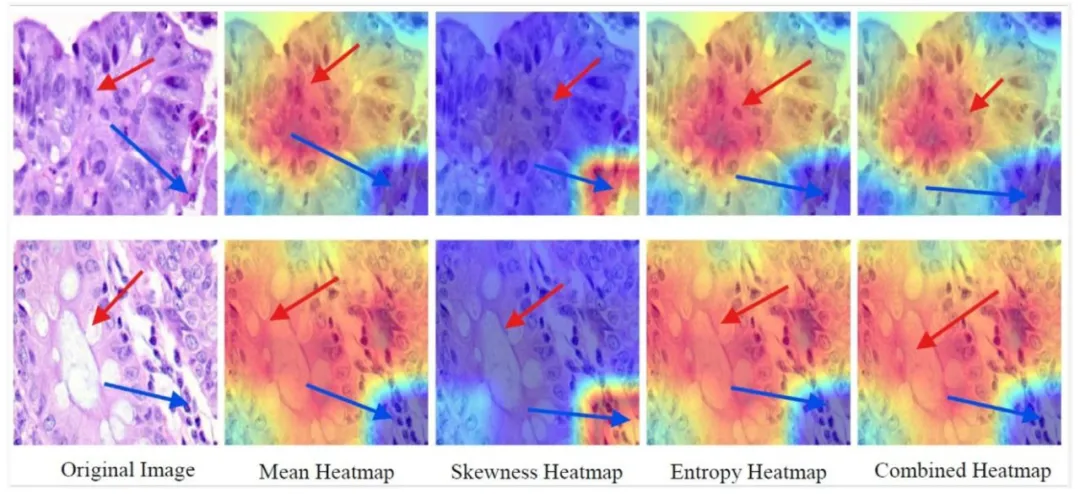

Fig. 7. SFMOV-based heatmap visualization showing a colon adenocarcinoma image predicted as colon adenocarcinoma (row 1) and a benign colon image predicted as benigncolon (row 2). The pathological area is indicated by the blue arrow, whereas the red arrow indicates the healthy tissue/the transition zone

图7. 基于SFMOV的热图可视化,展示了被预测为结肠腺癌的结肠腺癌图像(第1行)和被预测为良性结肠的良性结肠图像(第2行)。蓝色箭头指示病变区域,红色箭头指示健康组织/过渡区。